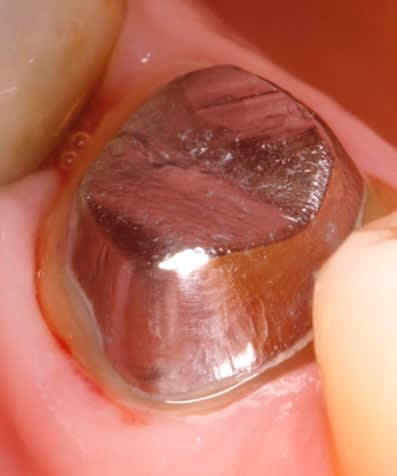

regardes celui là , il est pas bo ? aller hop a refaire :-(

Img 20171218 183744 kdrizc - Eugenol

> regardes celui là , il est pas bo ? aller hop a refaire :-(

Bien poli pourtant. celui là ne l'est pas..... A refaire. -)))